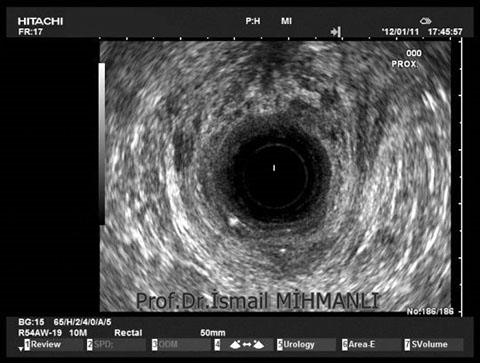

Crohn hastasında perianal enflamasyon içinde hava

Crohn hastasında perianal enflamasyon